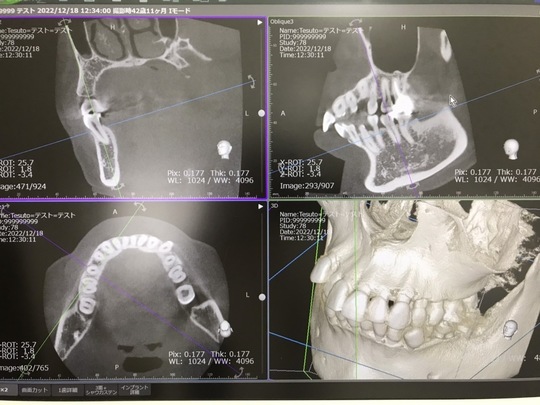

歯科用CTを導入しました。

さて、当院では、より安全な治療を行うため歯科用CTを導入しました。

従来のレントゲン写真では、二次元の画像になるため、

立体的な情報を得ることができません。

CT画像は、立体的に撮影できるため、より精密な情報を得ることができます。

例えば、親知らずの抜歯では、顎の中を通る神経や血管を傷つけないようにしなければ

いけませんが、CT画像により正確に位置がわかるようになり、安全に抜歯を行うことが

できます。

他にも根の治療では、レントゲン写真ではわからない、複雑な根の形状や破折などを

診断する事ができます。

CTの導入で、より安全正確な治療を提供させていただきます。

ご不明な点がございましたら、スタッフにお問合せ下さいね。